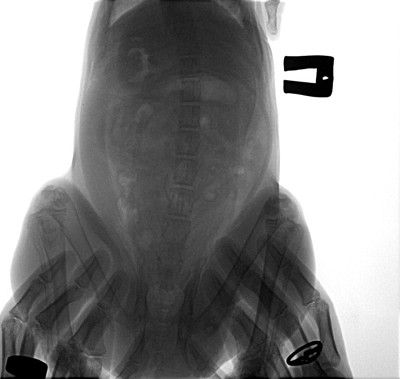

Толфедин

Толфедин 136 фотографий